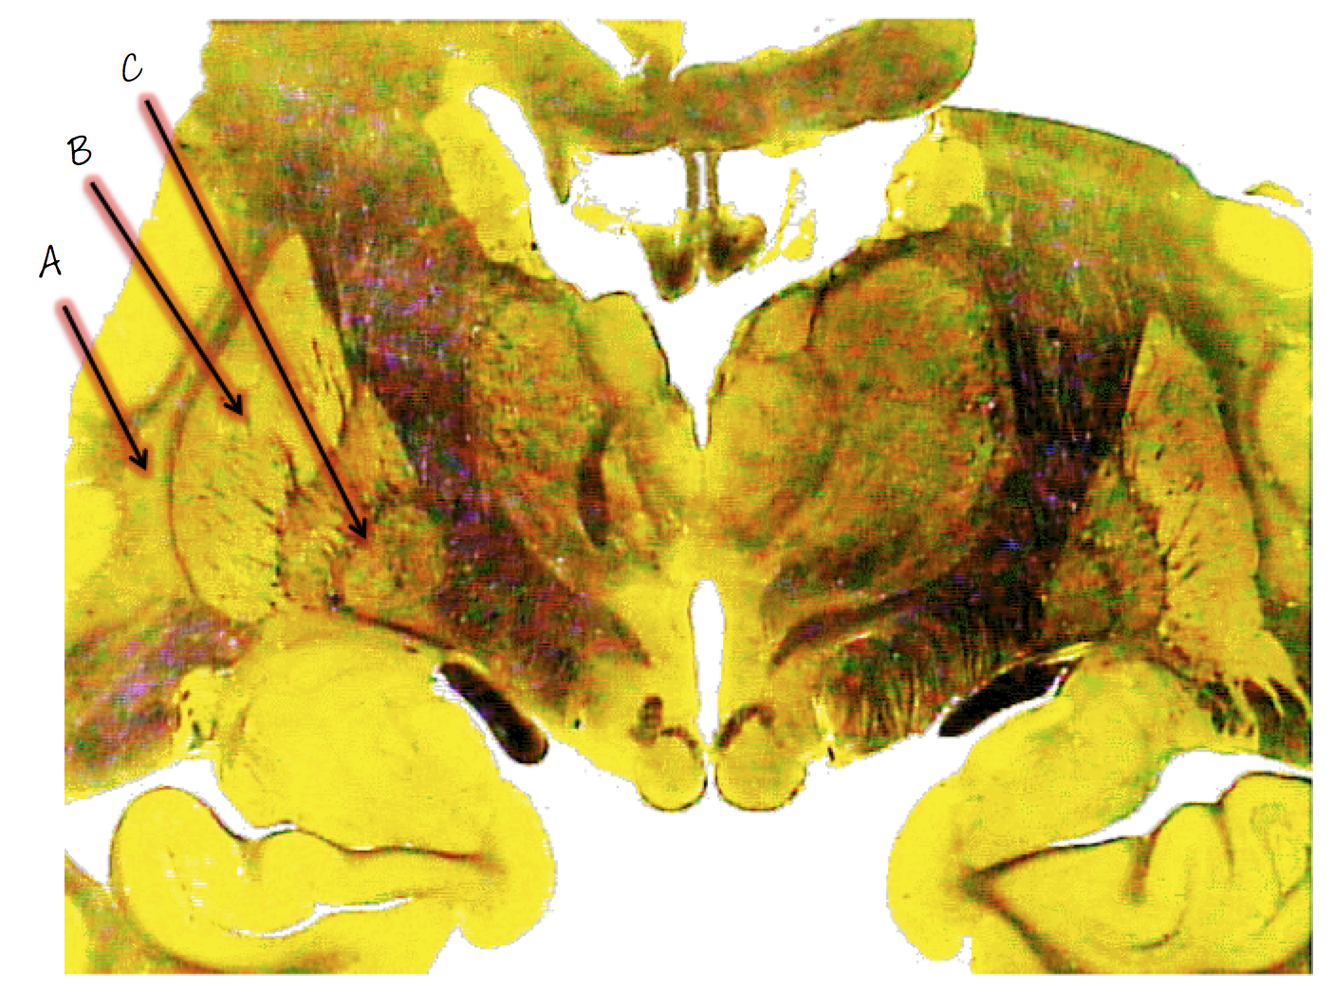

A; mammillary body

B; third ventricle

C; hypothalamus

D; optic tract

E; uncus